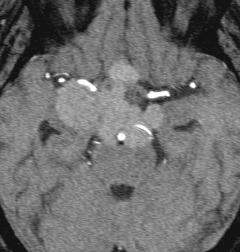

8歳で両側の視力低下が生じました。眼科では精神的なものと診断されて,4ヶ月くらいで右視力 0.4(耳側半盲),左指数弁となりました。のう胞性頭蓋咽頭腫で大きな骨化を伴うもので1月くらいの間に全盲になるかもと判断しました(失明寸前です)。

矢印の先に見えるように下垂体は正常の形態です。この画像から灰白隆起の左後方,乳頭体の前方が腫瘍発生母地ということがわかります。尿崩症もなく下垂体機能は正常です。経鼻的な内視鏡手術で腫瘍の大部分を摘出すれば下垂体機能は廃絶します。

とにかく失明を避けるために急いで経蝶形骨洞手術(transsphenoidal-transtuberculum sellae approach)で腫瘍のう胞の減圧をしました(緑の矢印の経路 by 函館中央病院加藤功先生)。その後に前頭開頭で腫瘍を全摘出しました(右側の画像)。尿崩症はでましたが下垂体前葉機能は正常です。

右視力 0.45,左明暗弁の視力が残りました。でももし,経鼻手術をしないでいきなり開頭すればおそらく全盲になっていた例です。